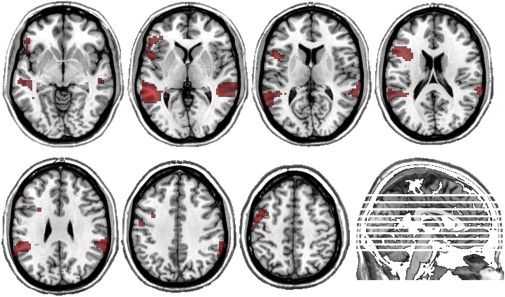

随着医学和神经科学的发展,人类对智力的研究已经进入更高的维度。fMRI这样的影像学手段,被用于评估大脑的区域功能表现,分子水平的研究使我们更深入的理解智力的原理。

fMRI定位的语言能力的功能和解剖位置关联性